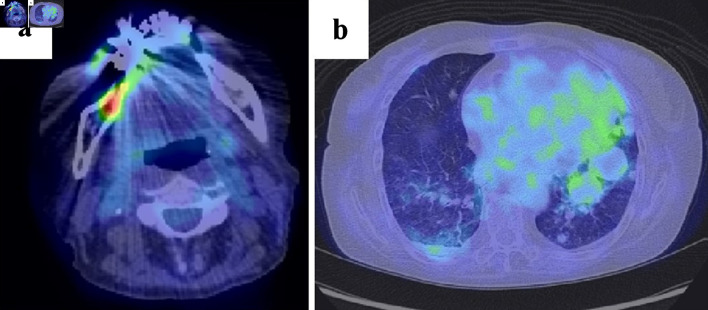

Plasmablastic lymphoma (PBL) is a malignant lymphoma with poor prognosis that occurs in immunocompromised and elderly patients. We describe the case of a 75-year-old woman with PBL as a methotrexate-associated lymphoproliferative disorder (MTX-LPD). She presented with multiple oral ulcers and mass-like shadows in the lung fields. Biopsy of the oral ulcer revealed medium to large irregular round monotypic B cells positive for cluster of differentiation (CD)138, CD79a, immunoglobulin λ, and Epstein-Barr virus-encoded small ribonucleic acid in situ hybridization, and PBL was diagnosed. The patient showed negative results for human immunodeficiency virus and had a history of taking MTX for rheumatoid arthritis, suggesting MTX-LPD. Following discontinuation of MTX, the oral ulcers resolved 1 month later without recurrence, and lung lesions decreased in size over time. Because MTX-LPD can take the form of PBL and may resolve with MTX withdrawal alone, therapeutic interventions should be carefully considered. While PBL is typically highly aggressive and requires prompt treatment, MTX-LPD cases can sometimes resolve without further treatment, depending on the clinical course. However, in cases where the disease shows progression or when spontaneous regression does not occur, additional therapeutic interventions may be necessary to manage the disease effectively.